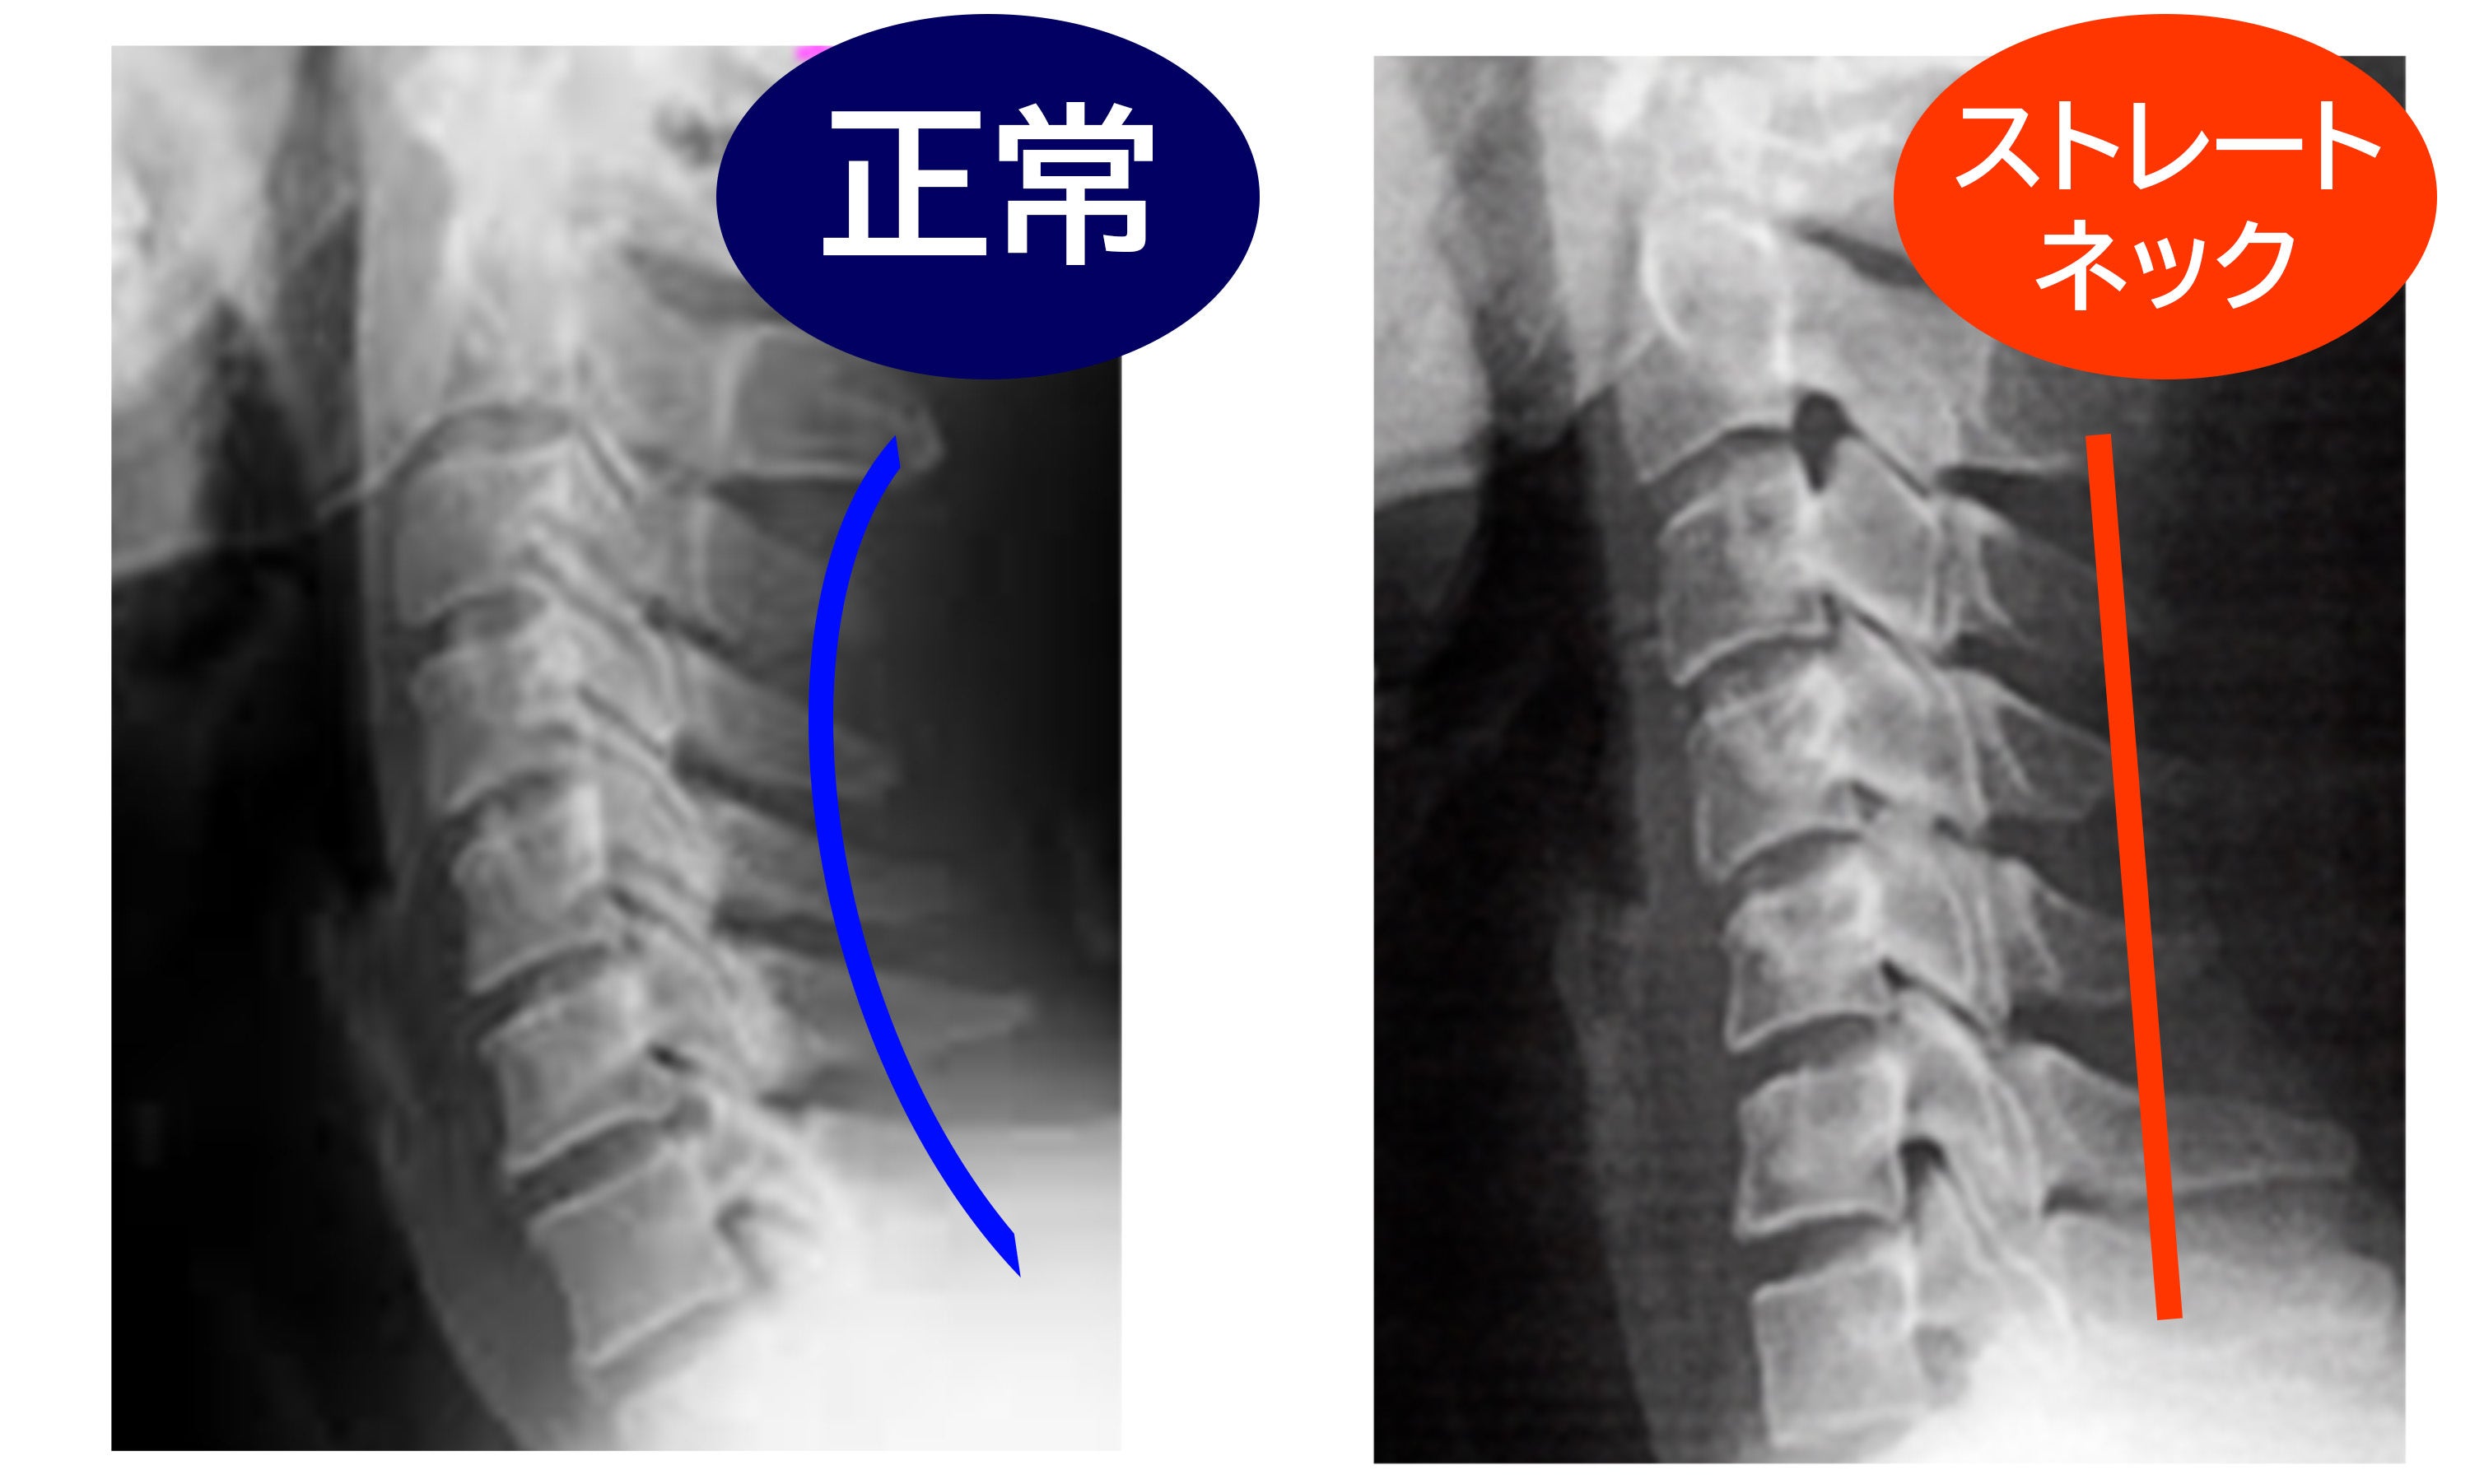

長時間のスマホ操作やデスクワークで、私たちの首は前に突き出しがちです。

その状態が続くと、本来S字を描くはずの頸椎の自然な湾曲(カーブ)**失われ、いわゆる「ストレートネック」のような姿勢に。

肩や首の違和感、頭まわりの重さ、姿勢の乱れなどにつながることもあります。独自のアーチ構造が背中全体をやさしく押し上げ、首を下から支えながら、頸椎を理想的なカーブへと導きます。